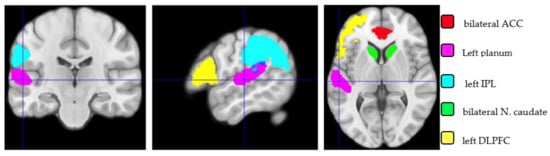

Comparisons between Regions of Interest. The ROIs are illustrated in Figure 1. Results (shown in Table 3) of the regions of interest (ROI) voxel-wise analysis did not show any statistical differences either in grey matter (VBM) or cortical thickness (SBM). Also, an analysis of the sub-ROI grey matter volume was separately performed mean-wise with a Bayesian statistic.

Figure 1. Illustration of the five regions of interest (ROIs): bilateral ACC, left planum temporale, left IPL, bilateral nucleus caudate and left DLPFC. The images are displayed using the neurosciences convention; the left hemisphere is on the left side.